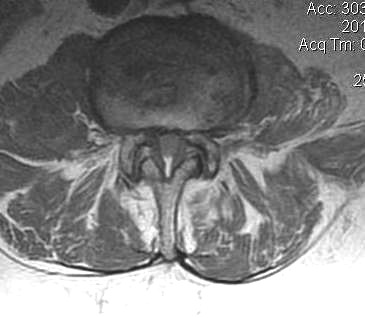

B. Axial slices

Findings

- no fat about dura

- trefoil shape canal

- lateral recess or foramina compression

- nerve root compression